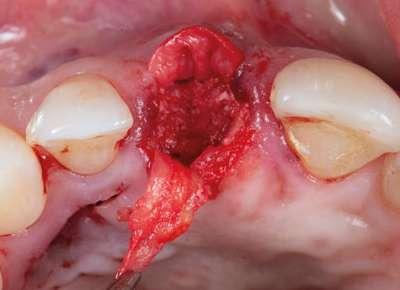

En este caso, podemos ver que tenemos un defecto óseo vestibular, se trata de un defecto de una sola pared de la zona a implantar. Intentamos planificar un implante inmediato y observamos la posibilidad de tener un buen anclaje apical por lo tanto nuestra primera opción va a ser la realización de un implante post extracción con regeneración de la pared vestibular mediate xenoinjerto óseo e injerto de tejido conectivo para mejorar el biotipo.

Cirugía

2.- Extraemos de manera meticulosa la raíz del diente afectado.

3.- Legramos toda la zona del lecho implantario con el fin de poder eliminar cualquier resto de tejido de granulación.

4.- Desepitelizamos en margen gingival.

5.- Tunelizamos el defecto vestibular para alojar el injerto de tejido conectivo.

6.- Colocamos injerto de tejido conectivo.

7.- Interponemos membrana reabsorbible entre tejido conectivo y alveolo.

8.- Realizamos osteotomía mediante férula quirúrgica utilizando fresa piloto.

21 eldentistamoderno mayo/junio 2024

caso clínico

9.- Seguimos preparando el lecho utilizando fresado biológico con la OsseoShaperTM

10.- Colocamos implante Nobel Biocare N1TM TiUltra de 3,5x13.

11.- Observamos el torque obtenido de 50N por lo tanto podemos realizar carga inmediata.

12.- Colocamos aditamento N1TM Base XealTM con el fin de trabajar la prótesis a nivel gingivall.

13.- Colocamos pilar provisional.

14.- Rellenamos el gap con creos xenogainTM, compactando para que el hueso llegue lo más apical posible y cubra la superficie implantaria expuesta.

15.- Cortamos pilar provisional y adaptamos el TempShellTM con composite. Podemos comprobar la predictibilidad en cuanto a la posición 3D planificada de nuestro implante.